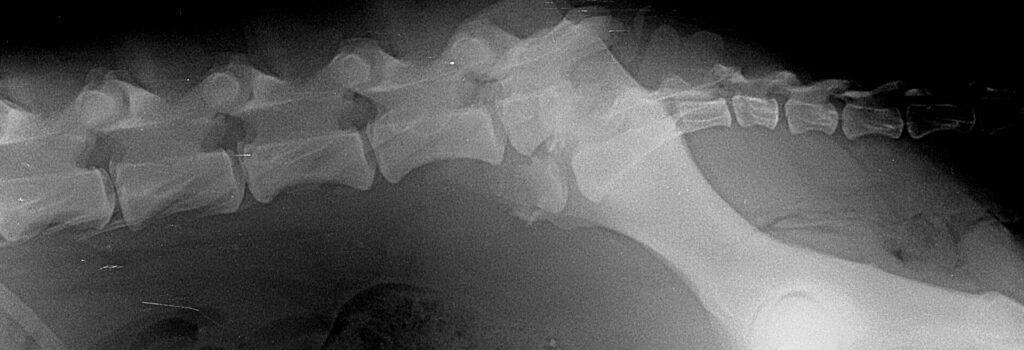

Πλάγια ακτινογραφία οσφυοϊερής μοίρας της ΣΣ. Απεικονίζονται: α) κάταγμα στο οπίσθιο τριτημόριο του σώματος του Ο7 και μετακίνηση του καταγματικού άκρου κοιλιακά και β) πλήρες εξάρθρημα μεταξύ του Ο7 και Ι1.